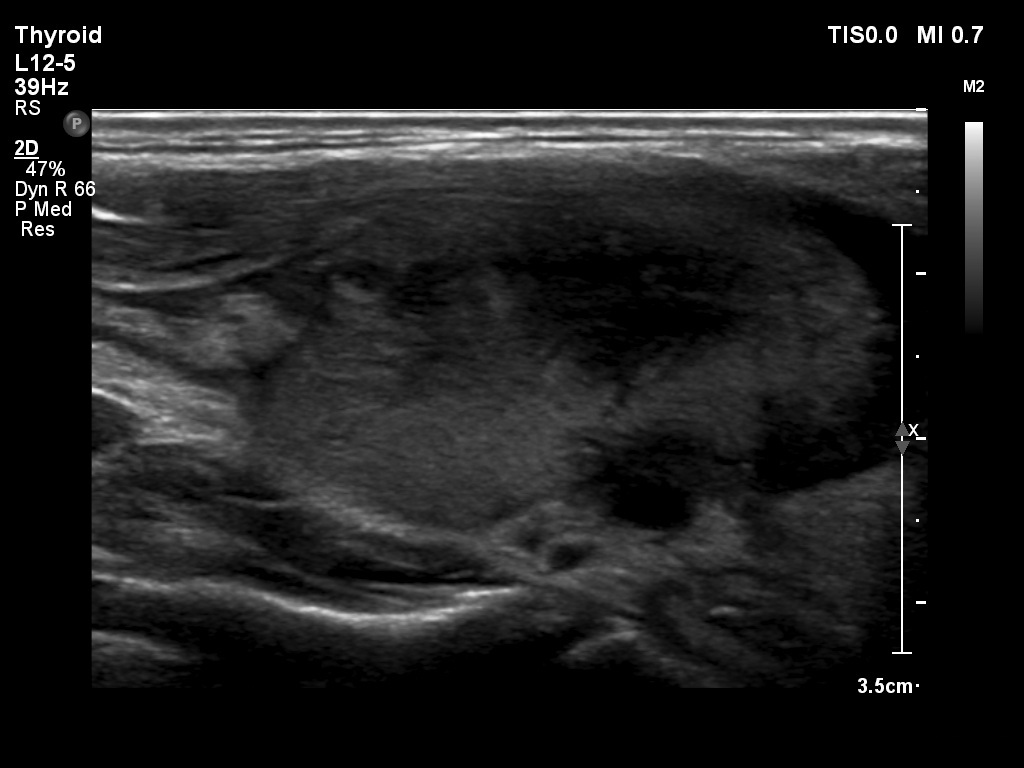

First examination (1st to 3rd rows of images):

Ultrasonography: Both lobes presented hypoechogenic ill-defined areas. The echogenicity index was 80% in the right lobe while 20% in the left thyroid. The vascularization was significantly decreased.

Elastography demonstrated hard areas according to the hypoechogenic field in the left lobe while almost the entire right lobe proved to be hard.Cytological diagnosis: subacute, granulomatous de Quervain's thyroiditis.